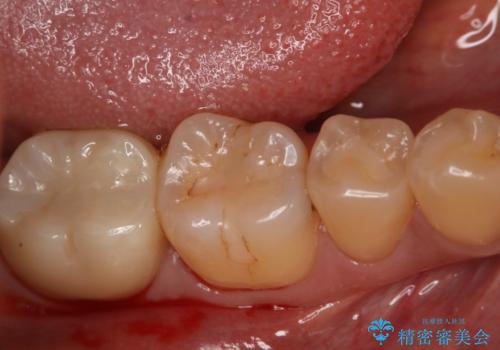

- 過去に他院で治療した部位が材料劣化を起こしていたため、セラミック治療を希望された患者様です。

切削量を考慮し、セラミックインレーを選択しました。

虫歯が深かったので、CRを詰めた上で形態を整えています。